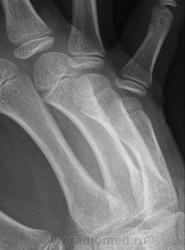

Остеоэпифизеолиз о/ф III пальца.

Спасибо Валентин Львович за обработку изображений, в данном случае остеоэпифизиолиз проксимальной фаланги 3п.. В косой проекции кстати даже четко видно ступеньку.